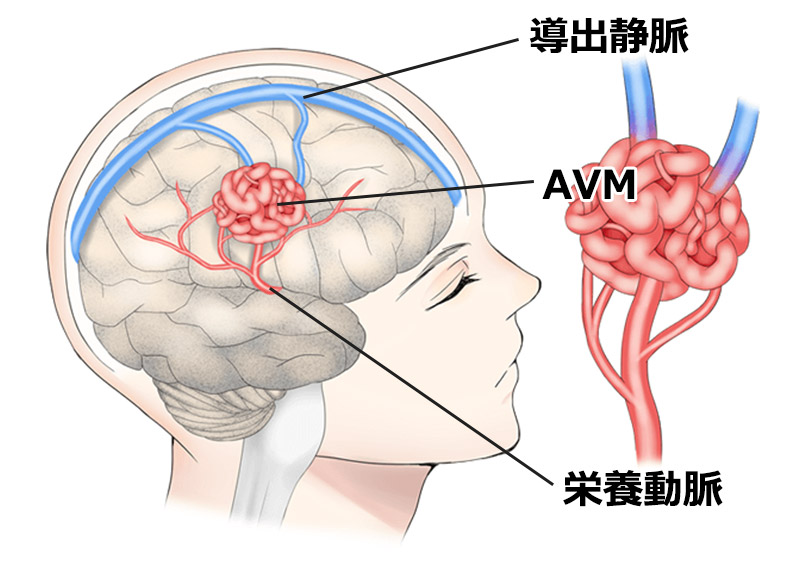

動静脈奇形(AVM)は、動脈と静脈の間の血液の流れを妨げる、まれな非癌性の血管のもつれです。

血液が動脈から毛細血管を通って静脈に流れるのではなく、AVM により血液が動脈から静脈に直接流れます。毛細血管は酸素を豊富に含む血液を細胞に分配することができないため、細胞が損傷を受ける可能性があります。

AVM 内を循環する過剰な血液は、特に若い成人の場合、出血を引き起こす可能性があります。これは、発作や脳卒中などの神経学的問題を引き起こしたり、致命的となる可能性があります。

AVM手術の目的

AVM手術の目的は、絡み合った血管を除去または縮小することで出血の可能性を防ぐことです。

これにより、血液が毛細血管を正常に流れることができます。